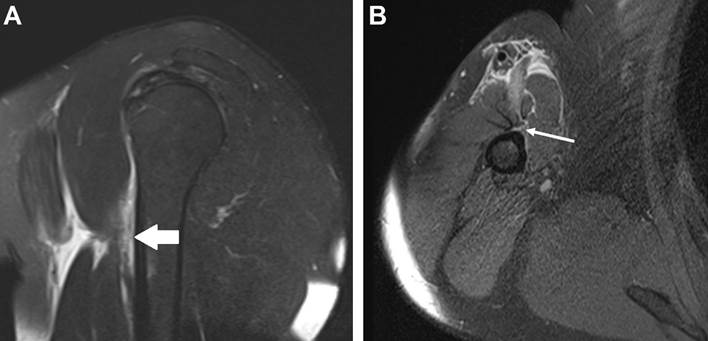

Refere hipertensão arterial sistêmica em tratamento, prática irregular de atividade física (musculação), porém não realiza há 4 meses. A ressonância magnética demonstrou rotura completa da junção miotendínea do peitoral maior (Figura 2), com tendinopatia com fissuras insercionais e intrasubstanciais infraespinhal e tendinopatia com rotura parcial do tendão subescapular. O ortopedista indicou, duas semanas após a lesão, o uso de medicação analgésica e repouso, sem a necessidade de fisioterapia. Três meses depois, o paciente apresenta limitação da movimentação do membro superior direito devido a dor, apesar da algia estar diminuindo, além de redução da força e da firmeza no membro e dificuldade de dormir do lado direito.

Figura 2: Ressonância magnética do ombro direito no corte sagital na sequência T2 com saturação de gordura (FAT SAT) (A) e no corte axial na sequência densidade protônica com saturação de gordura (DP FAT SAT) (B) demonstrando rotura completa da junção miotendínea do peitoral maior com efusão líquida local e conteúdo hemático associado (seta branca).